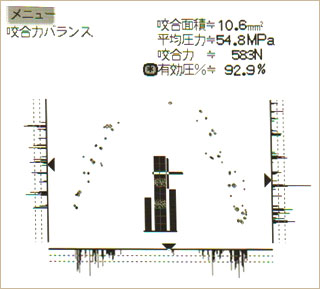

オクルーザーのデータを比較すると、治療前に左の方に偏っていた咬合力が、治療後はバランス良く回復しているのが分かります。